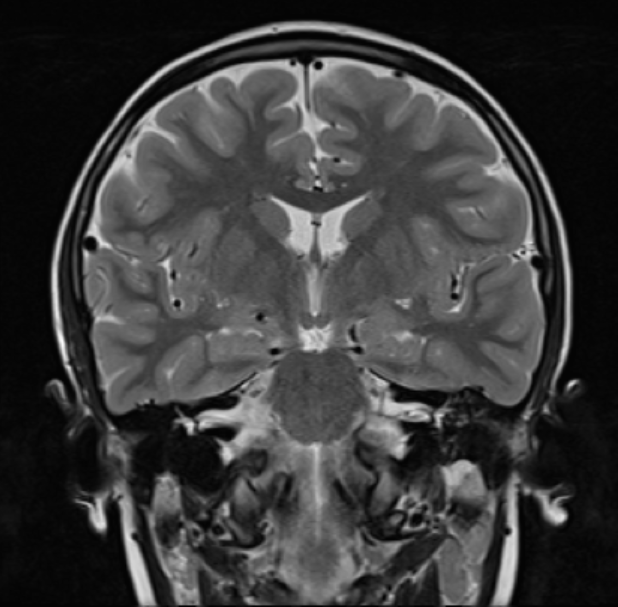

The MRI machine takes images from different angles, and our lab uses three main views of the brain.

• The coronal view shows horizontal brain slices from the top of the brain to the bottom. This image looks like a bird’s-eye-view perspective

Coronal View